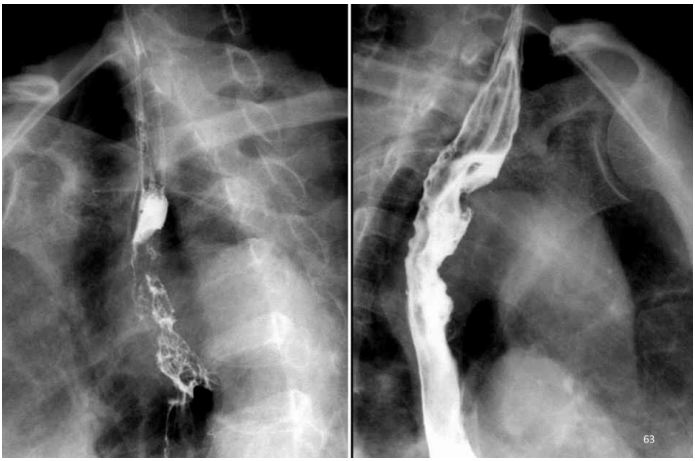

上消化道造影 食道癌